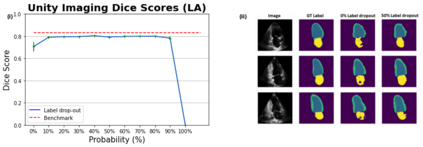

Echocardiography (echo) is the first imaging modality used when assessing cardiac function. The measurement of functional biomarkers from echo relies upon the segmentation of cardiac structures and deep learning models have been proposed to automate the segmentation process. However, in order to translate these tools to widespread clinical use it is important that the segmentation models are robust to a wide variety of images (e.g. acquired from different scanners, by operators with different levels of expertise etc.). To achieve this level of robustness it is necessary that the models are trained with multiple diverse datasets. A significant challenge faced when training with multiple diverse datasets is the variation in label presence, i.e. the combined data are often partially-labelled. Adaptations of the cross entropy loss function have been proposed to deal with partially labelled data. In this paper we show that training naively with such a loss function and multiple diverse datasets can lead to a form of shortcut learning, where the model associates label presence with domain characteristics, leading to a drop in performance. To address this problem, we propose a novel label dropout scheme to break the link between domain characteristics and the presence or absence of labels. We demonstrate that label dropout improves echo segmentation Dice score by 62% and 25% on two cardiac structures when training using multiple diverse partially labelled datasets.